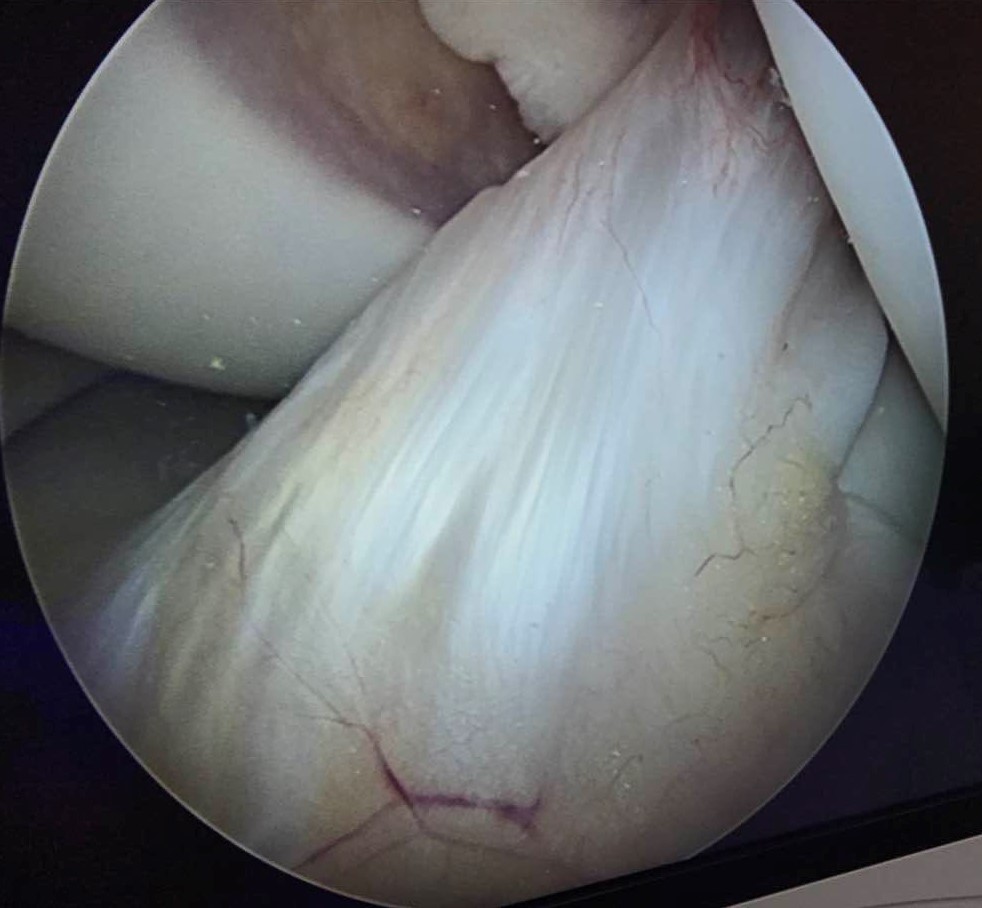

关节镜术中所见正常的前交叉韧带

膝关节内的交叉韧带有两条,分别是前交叉韧带和后交叉韧带。前交叉韧带位于髁间窝的前方,起于股骨外侧髁的内侧面,斜向前下方止于胫骨平台髁间嵴,有限制胫骨前移的作用。后交叉韧带位于髁间窝的后方,较前交叉韧带短,起自股骨内侧髁的内侧面,斜向后下方,止于胫骨平台后下方,具有限制胫骨后移的作用。